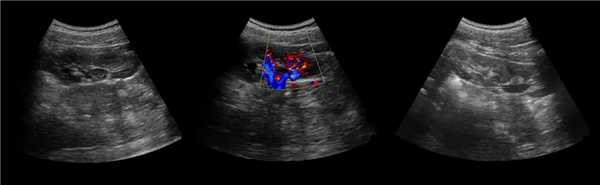

Клинический пример из первой группы. Пациент М., с хронической почечной недостаточностью. Трансплантация почки произведена от живого родственного донора. Трансплантат находится в правой подвздошной области. При нормальном функциональном состоянии трансплантата, показатели цветовой и спектральной допплерографии оценивались как удовлетворительные, с индексом резистентности не более 0,60 (рис. 1); показатели жесткости паренхимы почечного трансплантата при УЭСВ на различных участках составили от 20,05 до 29,18 кПа (рис. 2-4).

Рисунок 1. Ультразвуковое исследование в режиме цветовой и спектральной допплерографии в междольковых и сегментарных артериях у пациента М. Показатели кровотока в данном случае не изменены

У пациентов второй группы, при нормальных показателях клинико-лабораторных и допплерографических исследований, показатели жесткости почечного трансплантата составили 17,00-26,06 кПа.